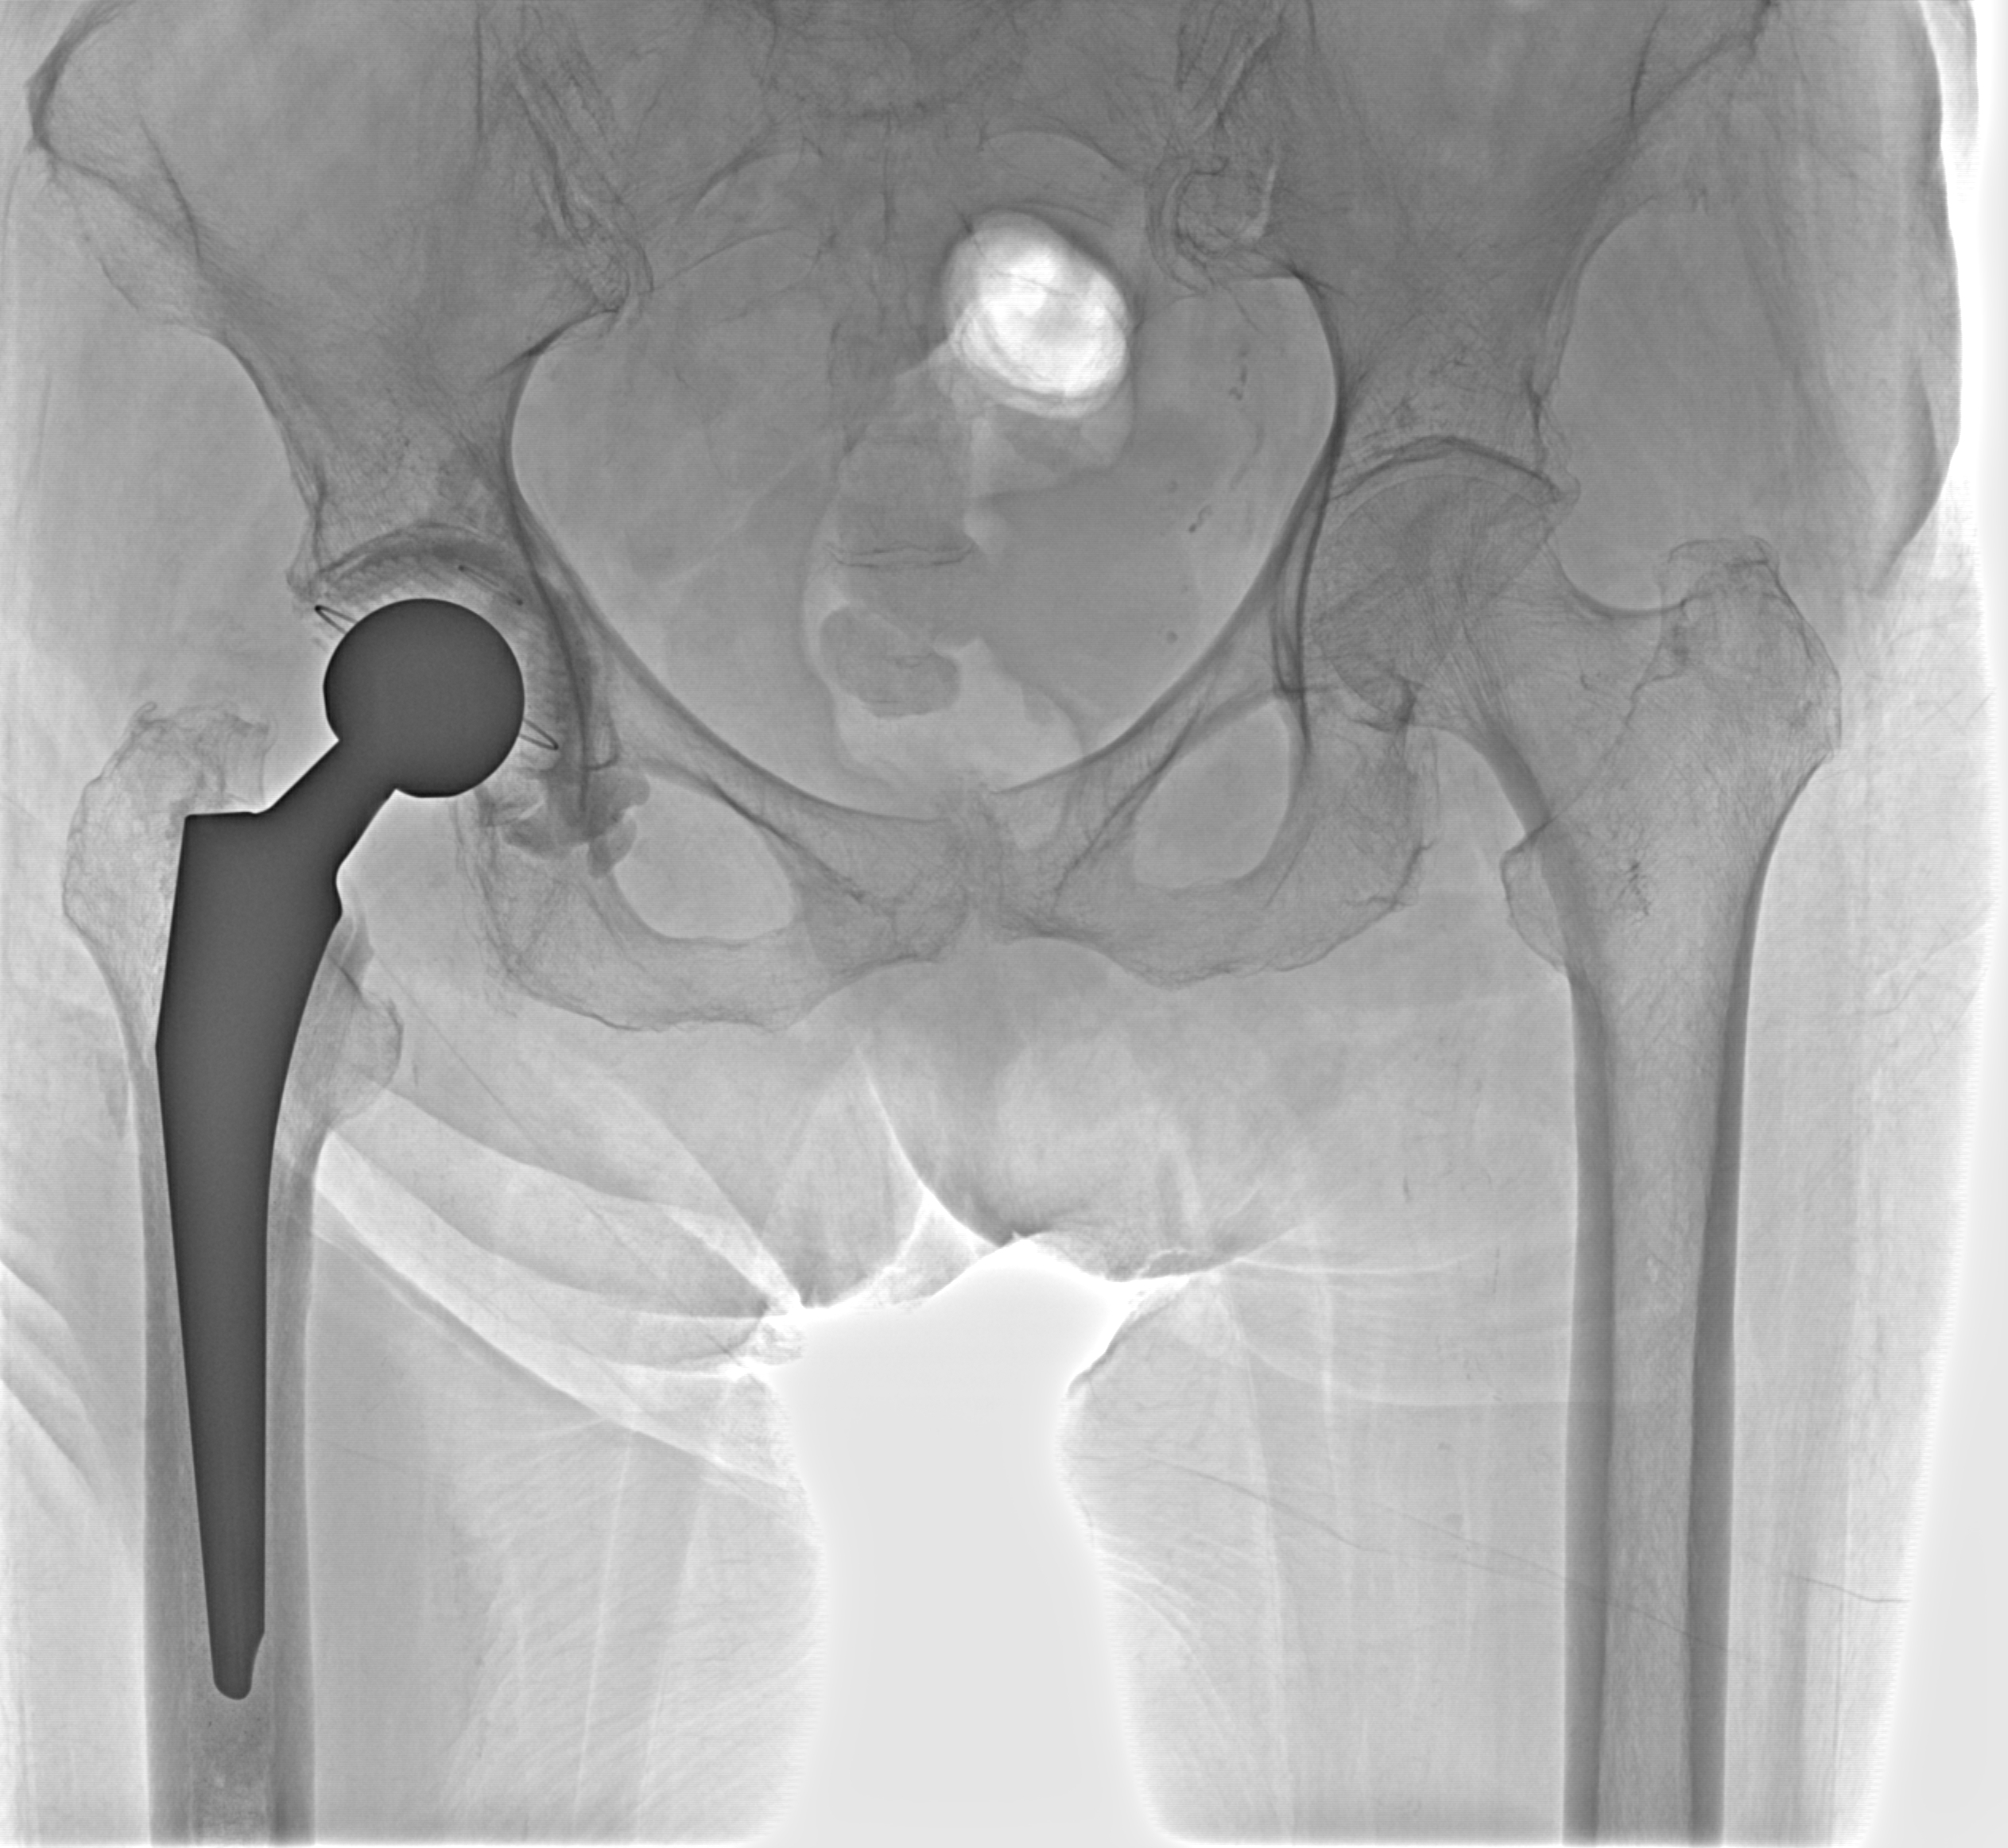

Эндопротез

Рентгенограммы

Рентген на дому: по вашему адресу приезжает врач-рентгенолог, травматолог-ортопед с мобильным рентгеновским аппаратом, проводит диагностику травмы или заболевания, делает необходимые рентгенограммы, дает рекомендации по дальнейшему лечению. Получить качественные снимки в домашних условиях возможно благодаря уникальной методике, разработанной МосРентген Центром для института  Склифосовского